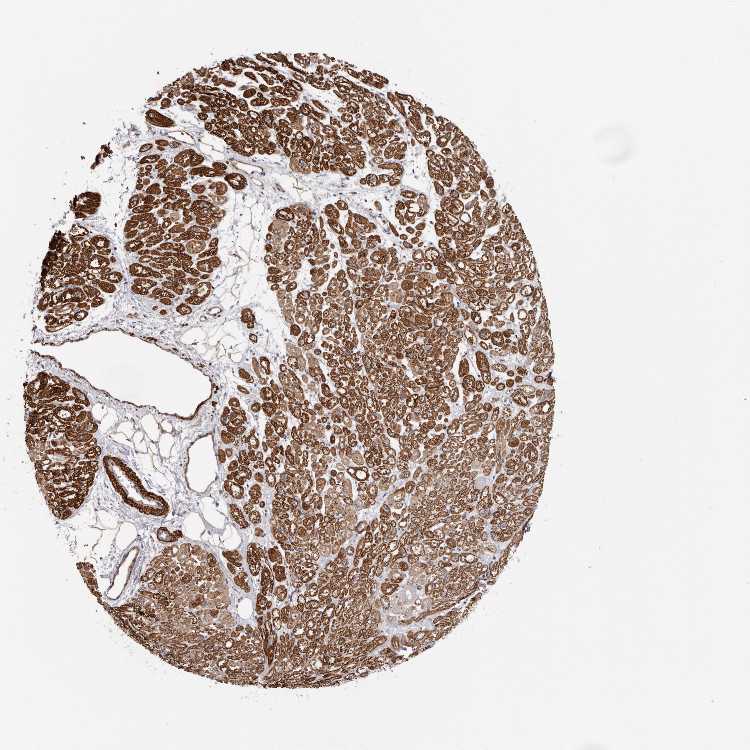

HEART MUSCLE - Antibody stainingi

Antibody staining in the annotated cell types in the current human tissue is reported as not detected, low, medium, or high, based on conventional immunohistochemistry profiling in selected tissues. This score is based on the combination of the staining intensity and fraction of stained cells.

Each image is clickable and will lead to virtual microscopy that enables deeper exploration of all samples and also displays staining intensity scores, fraction scores and subcellular localization as well as patient and tissue information for each sample.

Antibody HPA027481Antibody HPA028722

Cardiomyocytes Not detectedMedium